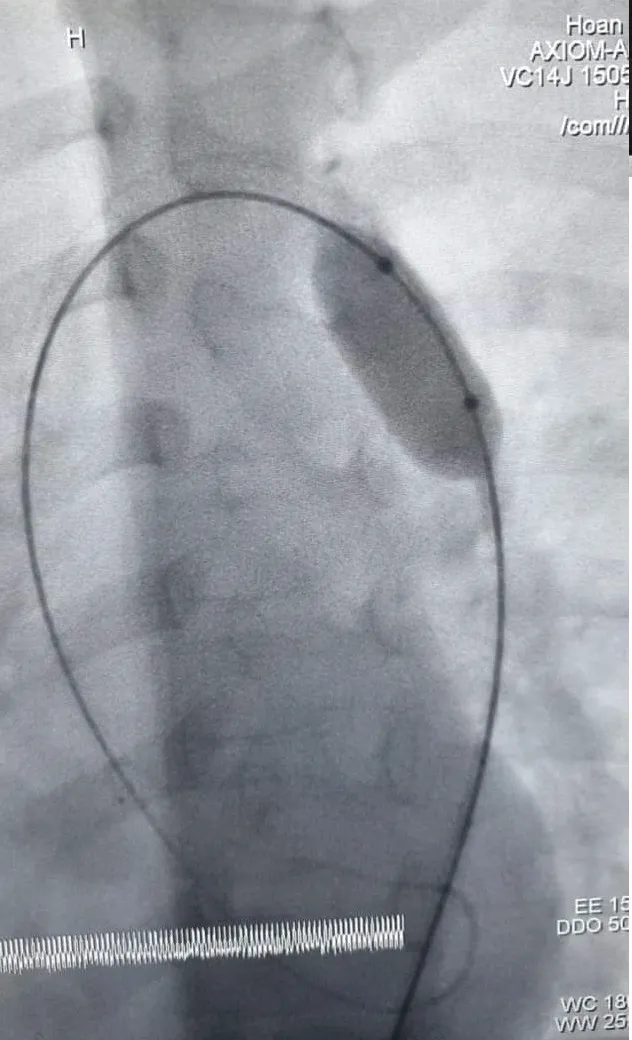

Can thiệp thành công bé 7 tuổi bị hẹp eo động mạch chủ  ảnh 1 Các bác sĩ nong mở rộng chỗ hẹp eo cho bệnh nhi

Do bệnh nhi nhỏ tuổi, nên bác sĩ đã chọn phương pháp xâm lấn tối thiểu nhất để can thiệp. Các bác sĩ tiến hành can thiệp qua da nong hẹp eo động mạch chủ. Quá trình can thiệp diễn ra trong khoảng 1 giờ đồng hồ. Sau can thiệp, bác sĩ đã mở rộng hoàn toàn chỗ hẹp, dòng chảy qua en gần như bình thường, không còn chênh áp qua chỗ hẹp; các chỉ số huyết động về bình thường. Bệnh nhi hồi phục sức khỏe tốt…